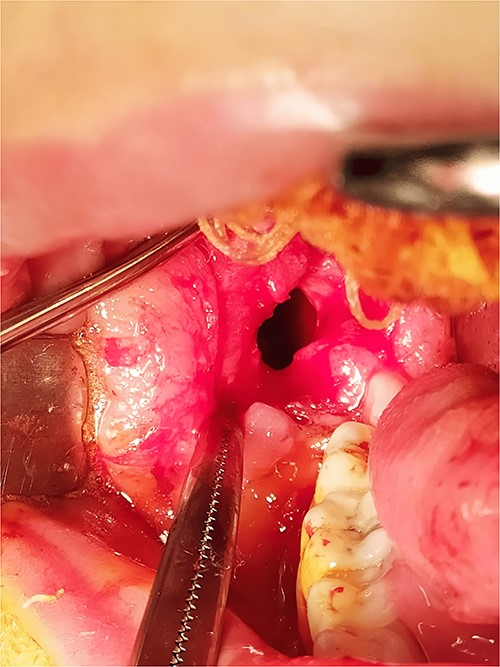

Under general anesthesia, an incision was made around the fistula to remove the overlying mucosa and expose the lesion. A 1 cm size window was made into the cyst cavity (Fig. 3). The cyst lining was sutured to surrounding mucosa. The cavity was kept open using a povidone iodine-saturated gauze, and it was replaced every 2 weeks. Follow-up radiograph (OPG) was recommended after 3, 6, 9 and 12 months (Figs 4 and 5).

Marsupialization procedure: exposure of the cystic cavity, 1 cm size window was made into the cyst cavity.